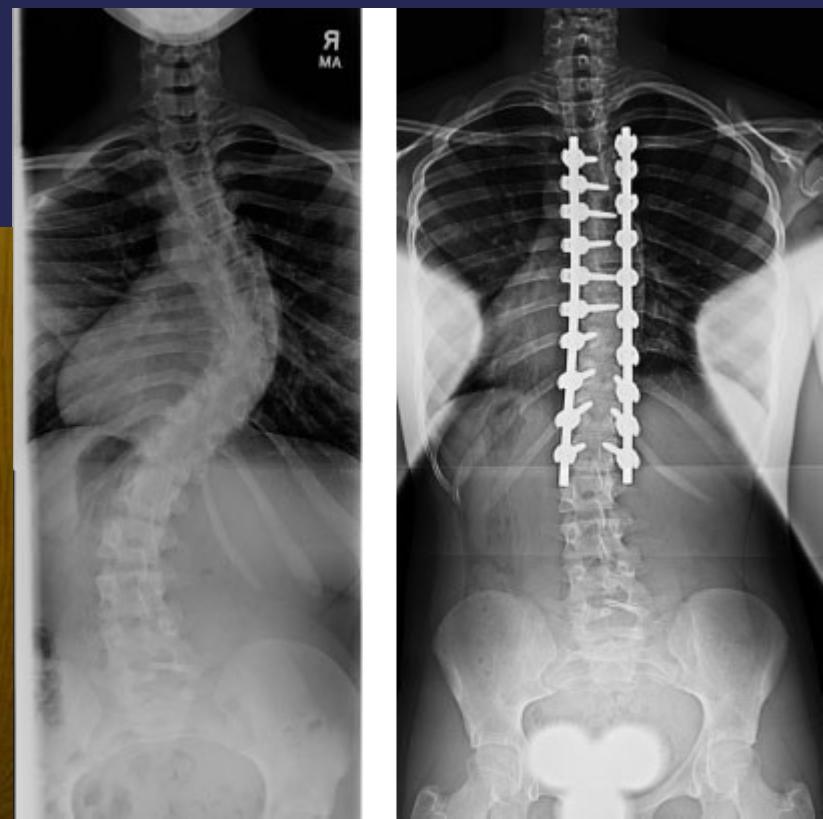

Surgical Treatment

Indications:

- Curves >40° in skeletally immature patients

- Progressive curves

Procedure:

- Correction

- Instrumentation

- Fusion

Surgery

- Adult documented progressive curves